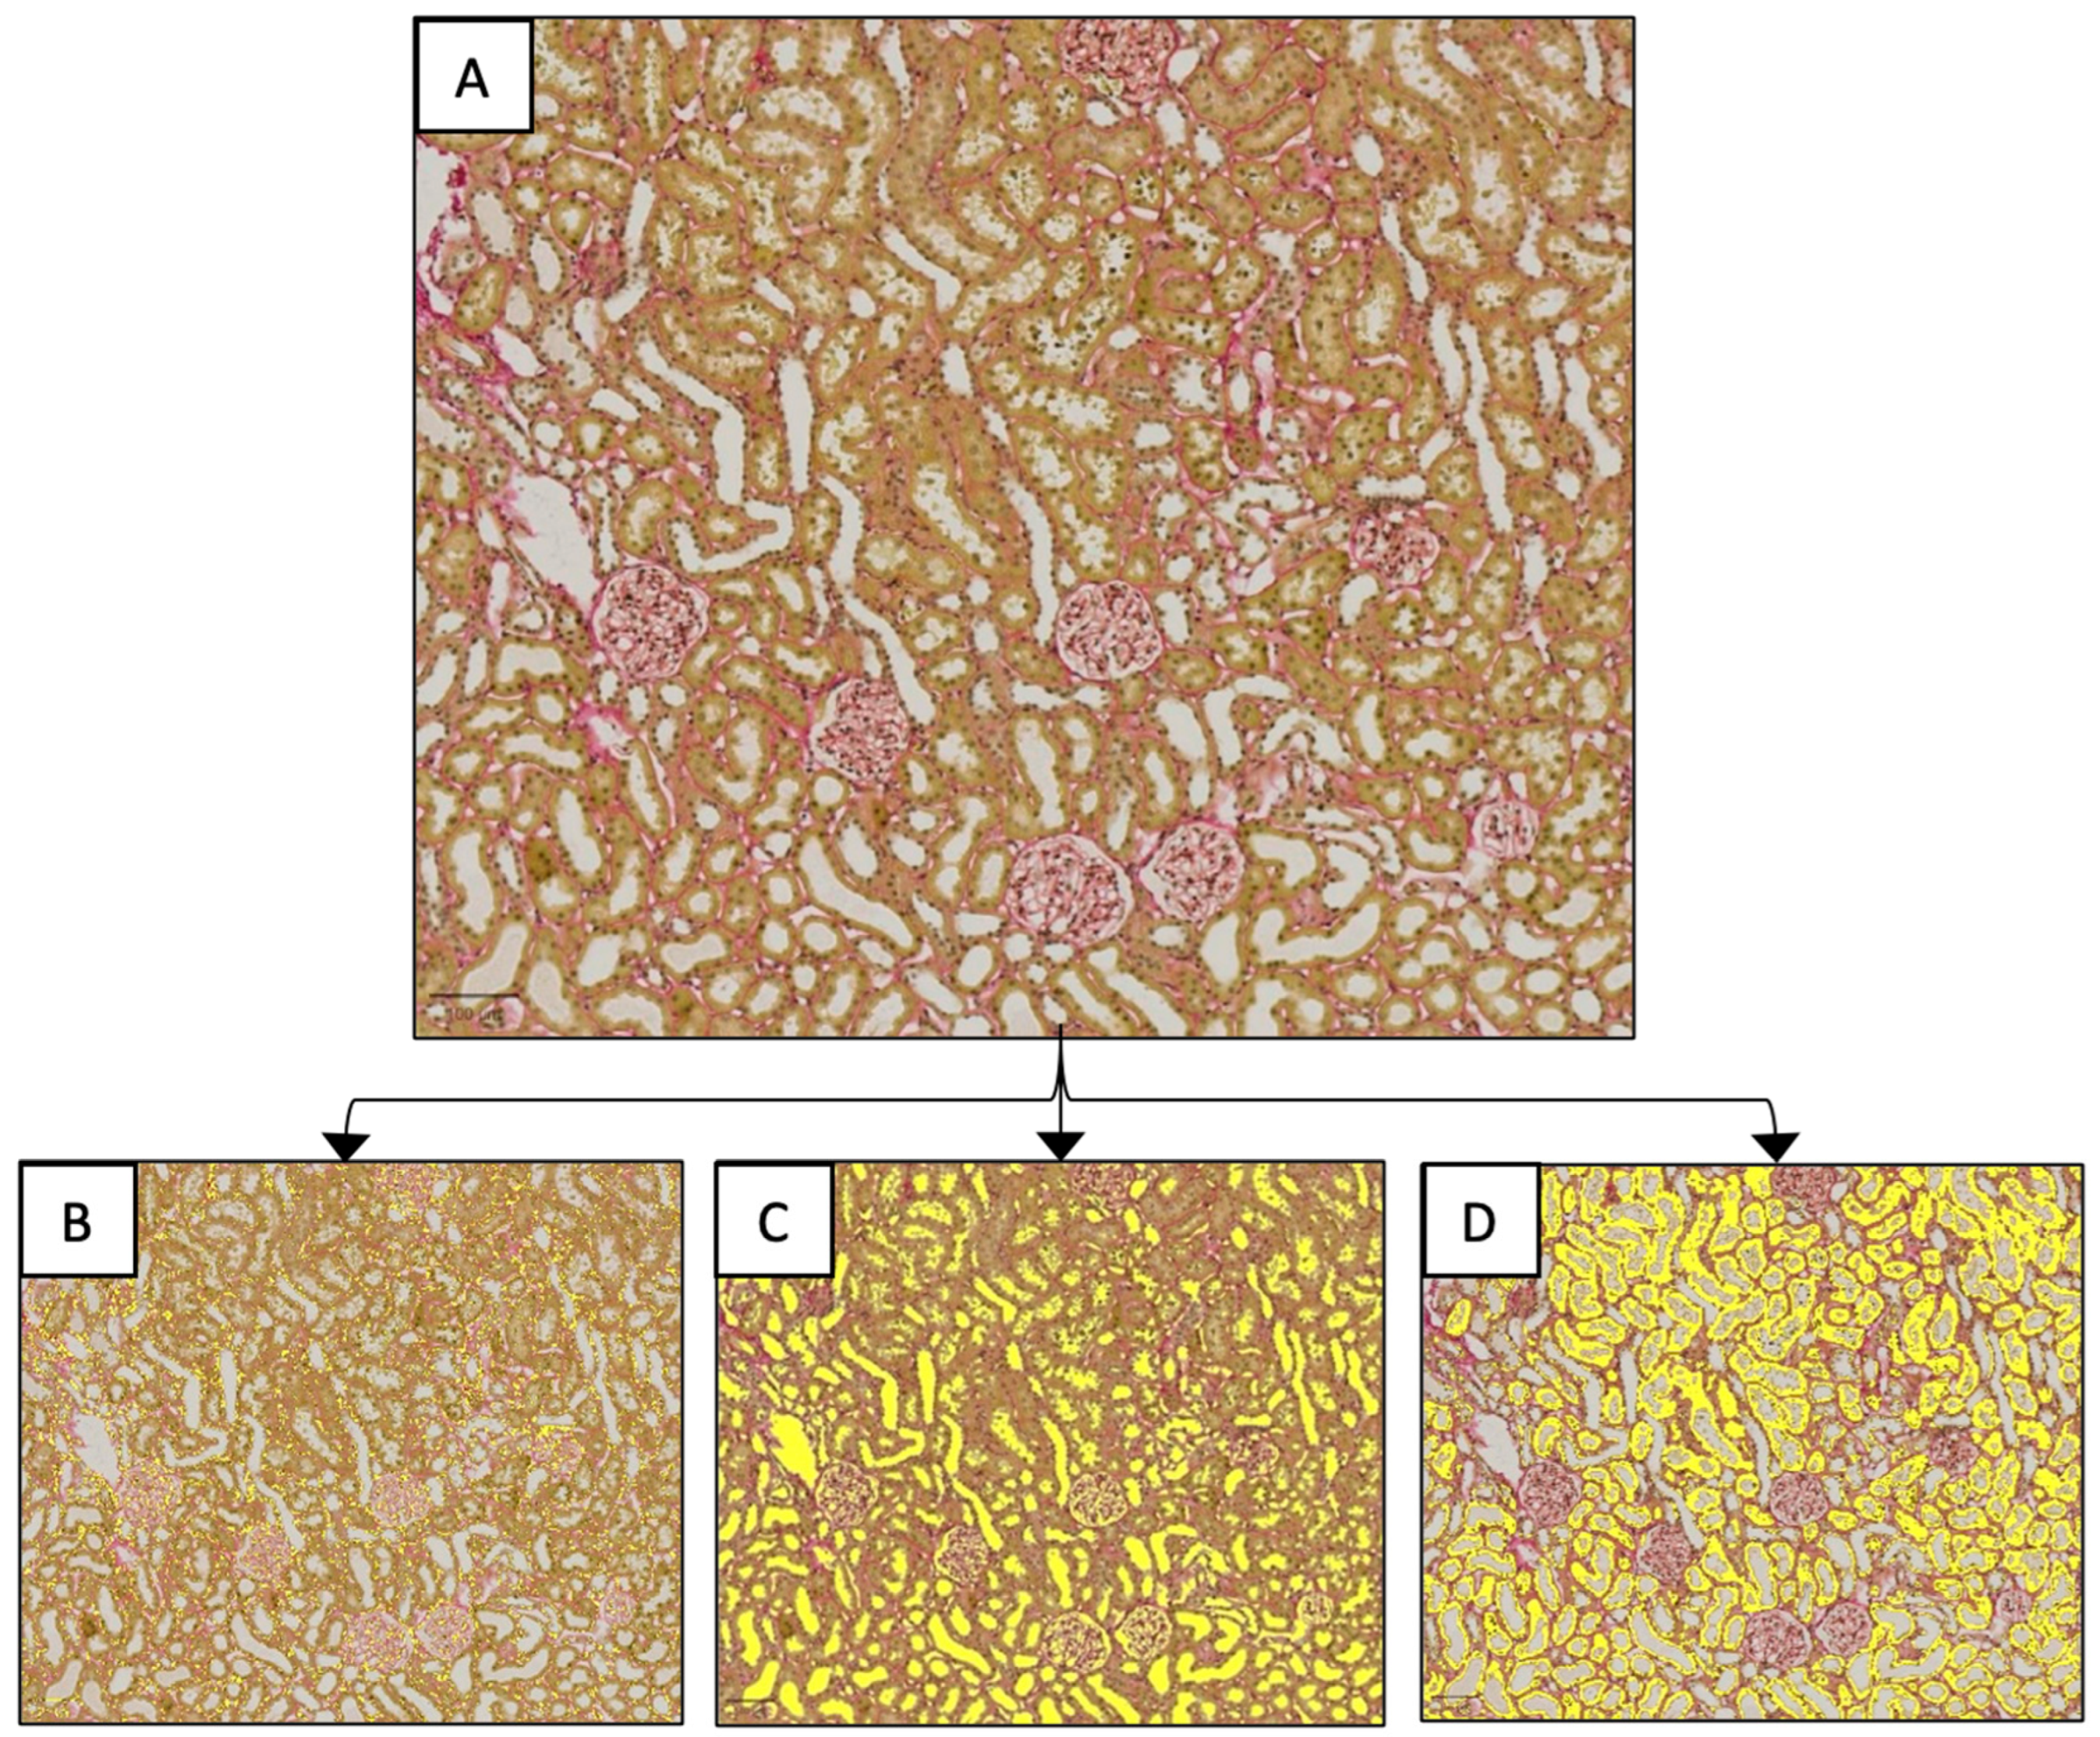

2.3. Renal Histology

3.4.2. Histological Tissue Architecture